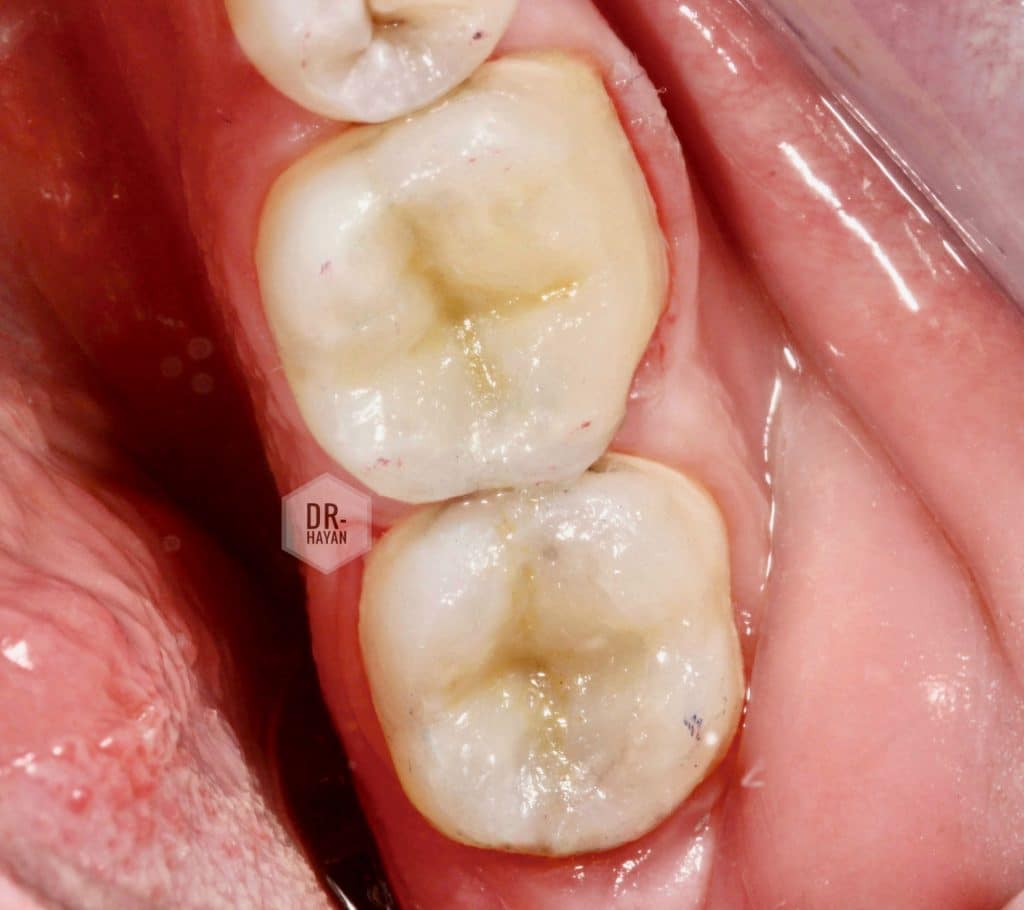

Final anatomy of lower 6

After Finishing and polishing use

enhance finishing system dentsply sirona

And EVE Finishing and polishing